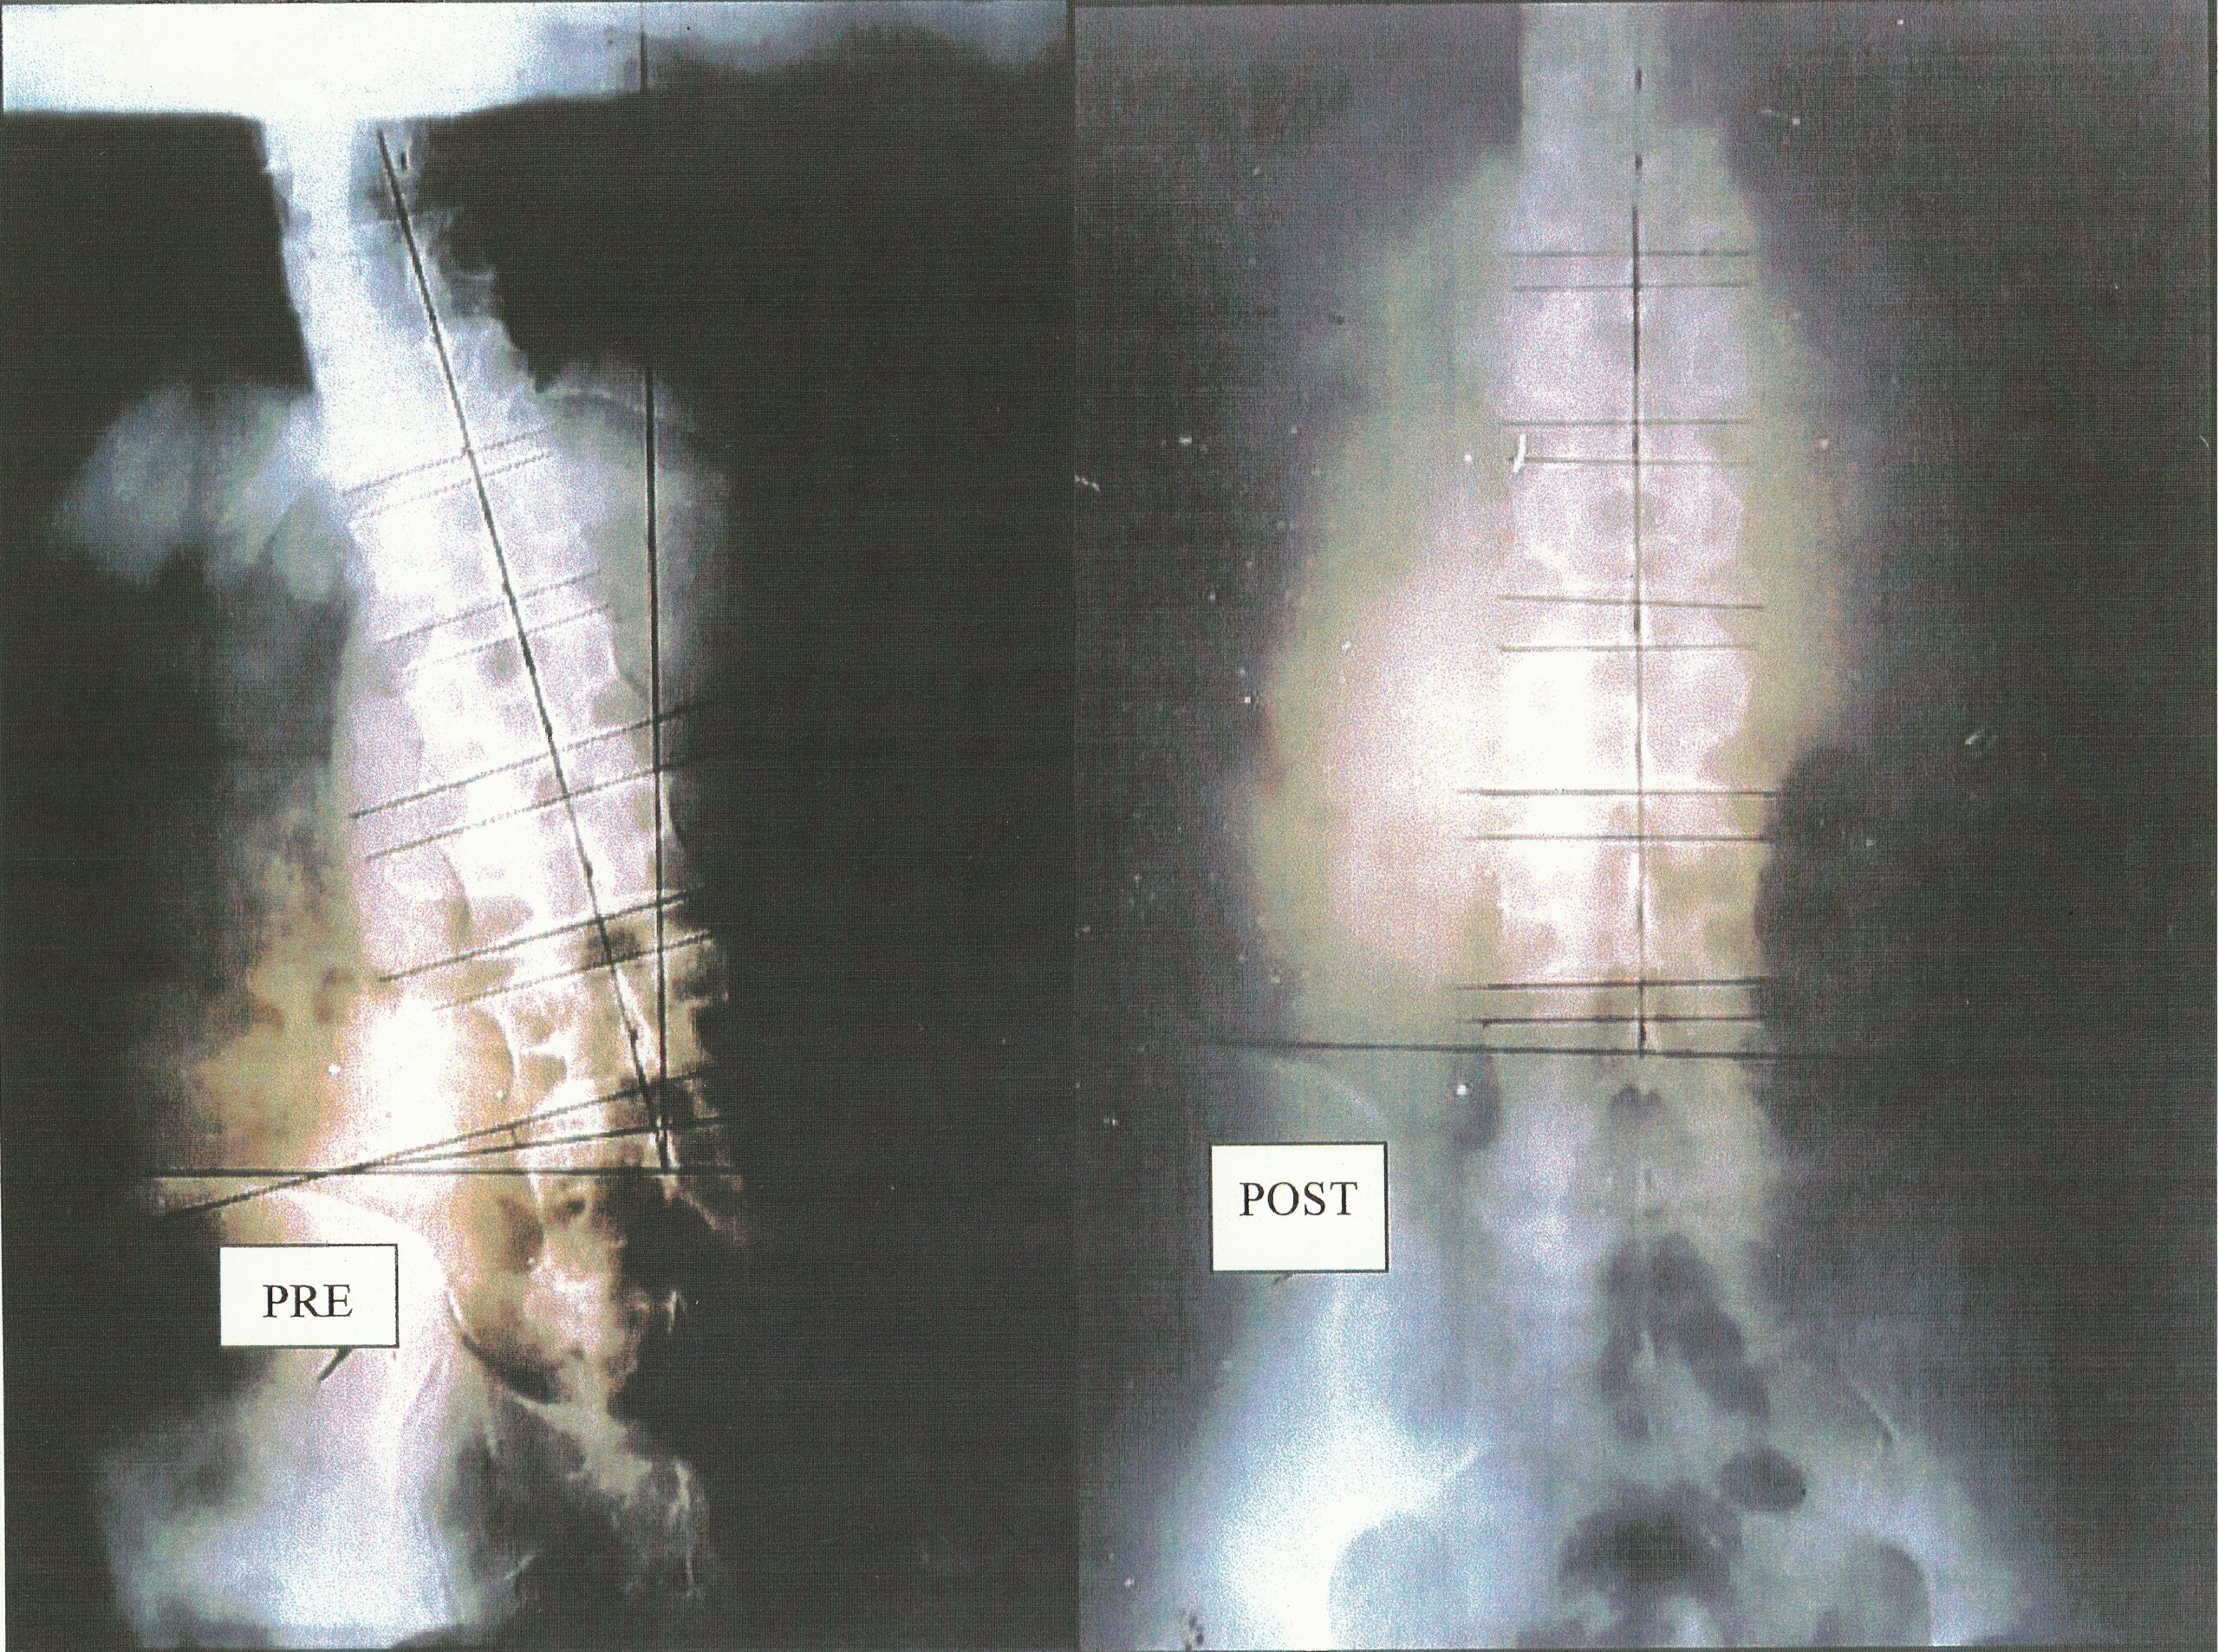

VISUAL EVIDENCE

科学的アプローチで見る施術の効果

第一頚椎(アトラス)を正常な位置に戻すと、重心が変わり腰椎は正しい配列を取り戻します。